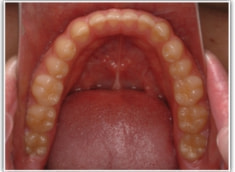

開咬(かいこう:オープンバイト)ケース

治療法:表の矯正(T21ブラケット)

(インプラントアンカーや外科矯正は行わず、エラスティックと機能訓練のみ)

治療後(2年2ヶ月後)